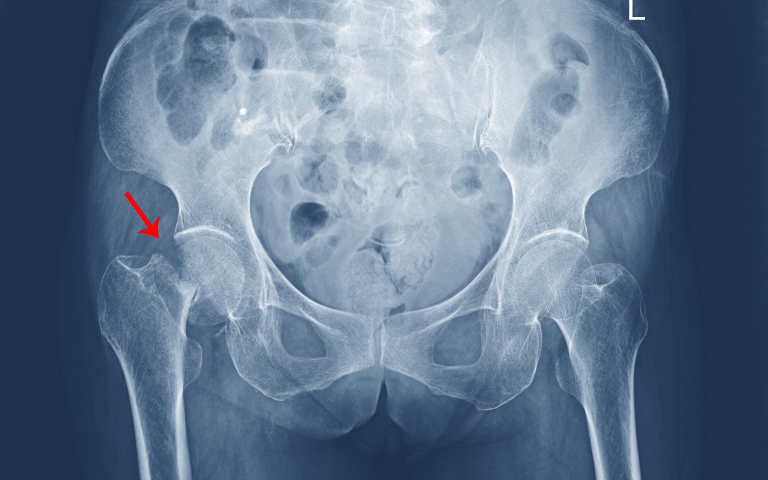

Identifying Severe Hip Damage

Not all hip fractures require replacement. Hip replacement is recommended when the fracture involves the joint surface, is displaced, or occurs in patients with pre-existing arthritis or weakened bone. Signs include severe hip pain, inability to walk, and reduced leg stability. Timely evaluation by an experienced Orthopaedic Specialist in Islamabad ensures the right treatment is chosen for optimal recovery.